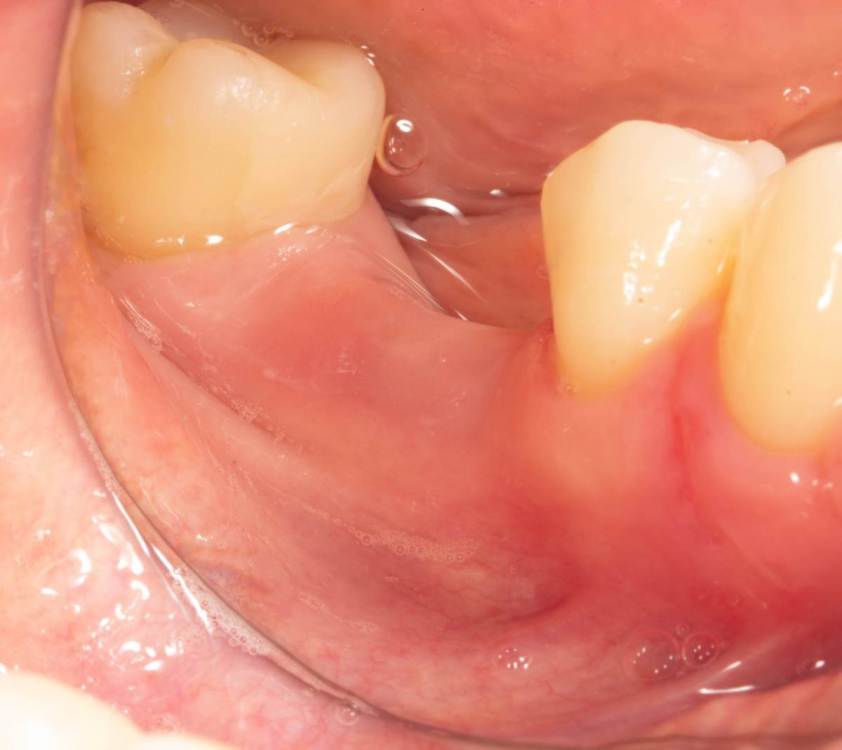

Женька Опубликовано 19 июня, 2023 Поделиться Опубликовано 19 июня, 2023 Здравствуйте, коллеги. Примерно с нового года начал ставить ТЛ имплантаты Дентиум. Что-то под заглушку (не поймал торки, представляете?). Что-то на низких формирвателях. И вот пришла пора протезирования, но отпустить к ортопеду не подготовив десну - не получается. Создал сам себе проблем, сегодня вот исправлял. Получилось неплохо? 3 Ссылка на комментарий

TIGER Опубликовано 20 июня, 2023 Поделиться Опубликовано 20 июня, 2023 Это ж не TL,cубкрестально же.А так я бы длиннее брал ССТ,с захватом соседей Ссылка на комментарий

Женька Опубликовано 20 июня, 2023 Автор Поделиться Опубликовано 20 июня, 2023 @TIGER в смысле это не ТЛ?))) Фото с редукцией не сделал. А то что, шейку погружал - так нужно было. Но это ТЛ. Поверьте) я был на имплантации) Ссылка на комментарий

АнтонТЛТ Опубликовано 20 июня, 2023 Поделиться Опубликовано 20 июня, 2023 Думаю имеется ввиду что имплантат TL установлен по протоколу BL Ссылка на комментарий

Женька Опубликовано 20 июня, 2023 Автор Поделиться Опубликовано 20 июня, 2023 @АнтонТЛТ мы же позиционируем платформу относительно зенита? Есть ли разница тогда, какой имплантат мы выбираем? Вообще весь смысл здесь был заложен в том, что толщина гребня была не очень. Хотелось поставить тонкий имплантат 3.6. Но рисковать тонкой платформой не хотелось, поэтому выбор пал на 4.8 платформу ТЛ и тело имплантата 3.6 1 Ссылка на комментарий

АнтонТЛТ Опубликовано 20 июня, 2023 Поделиться Опубликовано 20 июня, 2023 Конечно относительно зенита, не вдаваясь в подробности, для BL глубже зенита на 3мм, для TL вровень с зенитом. Ссылка на комментарий